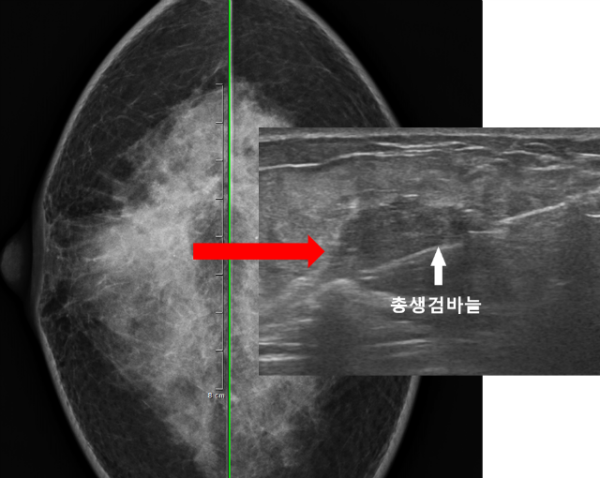

진찰상 만져지는 혹의 양상, 그리고 초음파상 관찰된 혹의 모양으로 보았을때 악성 가능성이 매우 높은 상태로 판단되어 조직검사의 필요성에 대해 설명드린후 내원 당일에 바로 총생검검사까지 진행하기로 하였습니다.

이 환자분도 마찬가지로 유방암이 매우 의심되는 상황이었기 때문에 유방초음파와 총생검검사 모두를 건강보험적용이 되는 급여검사로 전환하여 비교적 저렴한 비용으로 검사를 받으시도록 도와드렸습니다. (자세한 비용은 댓글이나 외래로 문의주시면 안내해드립니다.)

오른쪽 유방의 결절에 대해 안전하게 총생검검사를 시행하였으며 빠른 결과를 위해 응급으로 조직검사를 의뢰하였습니다. 3일만에 최종 결과를 확인할 수 있었습니다.